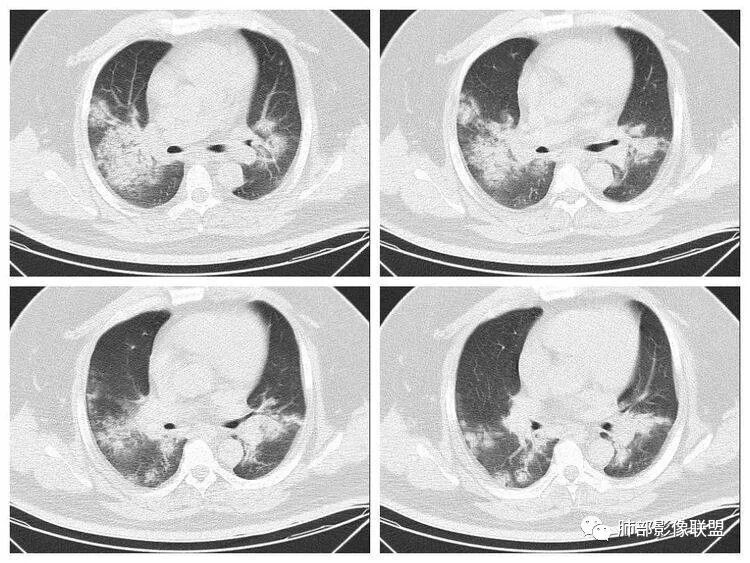

青年男性、急性病史、发热、咳嗽、常规抗炎无效病灶沿支气管血管束分布  GGO+实变边界模糊部分沿胸膜下分布哪几种可能?

南边:1、感染:间质分布——病毒、支原体,支原体一般树芽征明显,累及小气道多,而且临床轻,不太支持2、血管炎,需要相关病史3、肺水肿:心脏不大,无胸水、无中央间质增厚、小叶间隔增厚,不太支持4、PAP,病史影像表现都不支持初学者:可能是病毒,但是好像并不是我们常见的流感病毒实变为主,腺病毒?就是太多灶了一点

重症流感的定义出现以下情况之一者为重症病例1.持续高热>3天,伴有剧烈咳嗽,咳脓痰、血痰,或胸痛2.呼吸频率快,呼吸困难,口唇紫绀;3.神志改変:反应迟钝、嗜睡、躁动、惊厥等4.严重呕吐、腹泻,出现脱水表现;5.合并肺炎6.原有基础疾病明显加重。危重症流感的定义出现以下情况之一者为危重病例1.呼吸衰竭2.急性坏死性脑病3.脓毒性休克4.多脏器功能不全5.出现其他需进行监护治疗的严重临床情况。重症流感病毒肺炎的肺部影像以双肺多发磨玻璃影及实变影为主要表现,可合并少量胸腔积液,典型的H1N1双肺外带分布为主。随病程发展,部分患者出现实变及纤维化临床表现早期流感样症状:咳嗽、咳痰、发热、咽痛、全身酸痛。主要临床表现:肺炎、ARDS。患者咳嗽、咳痰、呼吸困难、氧饱和度低,发热、咽痛、全身酸痛,神志异常。甚至呼吸衰竭、休克,多器官衰竭等等。相关链接https://m.qlchat.com/topic/details?topicId=280000451285864

起病突然,高热,双肺多发磨玻璃影及实变影,胸膜下分布为主,不具有肺门分布优势,也没有小叶间隔增厚,一般会首先考虑病毒感染,尤其是甲流。